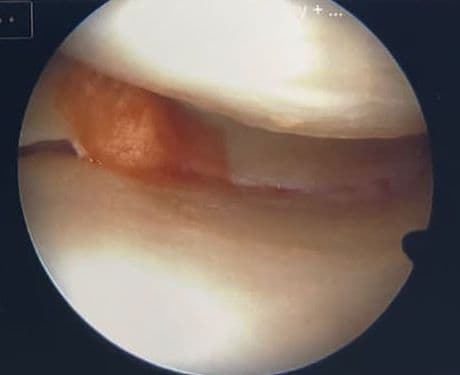

A torn meniscus injury requires careful management to maintain mobility while preventing further damage. This article outlines expert-recommended strategies for safe movement, highlighting the importance of gentle walking with supportive aids and avoiding knee-stressing activities like twisting or deep squats. It emphasizes low-impact exercises such as swimming and stationary cycling, complemented by physical therapy to strengthen surrounding muscles and enhance knee stability. Key signs to watch for include pain, swelling, and knee locking, with prompt medical consultation advised if symptoms worsen. Expert rehabilitation programs have proven effective in improving knee range of motion post-injury. Ultimately, balancing cautious activity with professional guidance supports optimal recovery and preserves knee function.